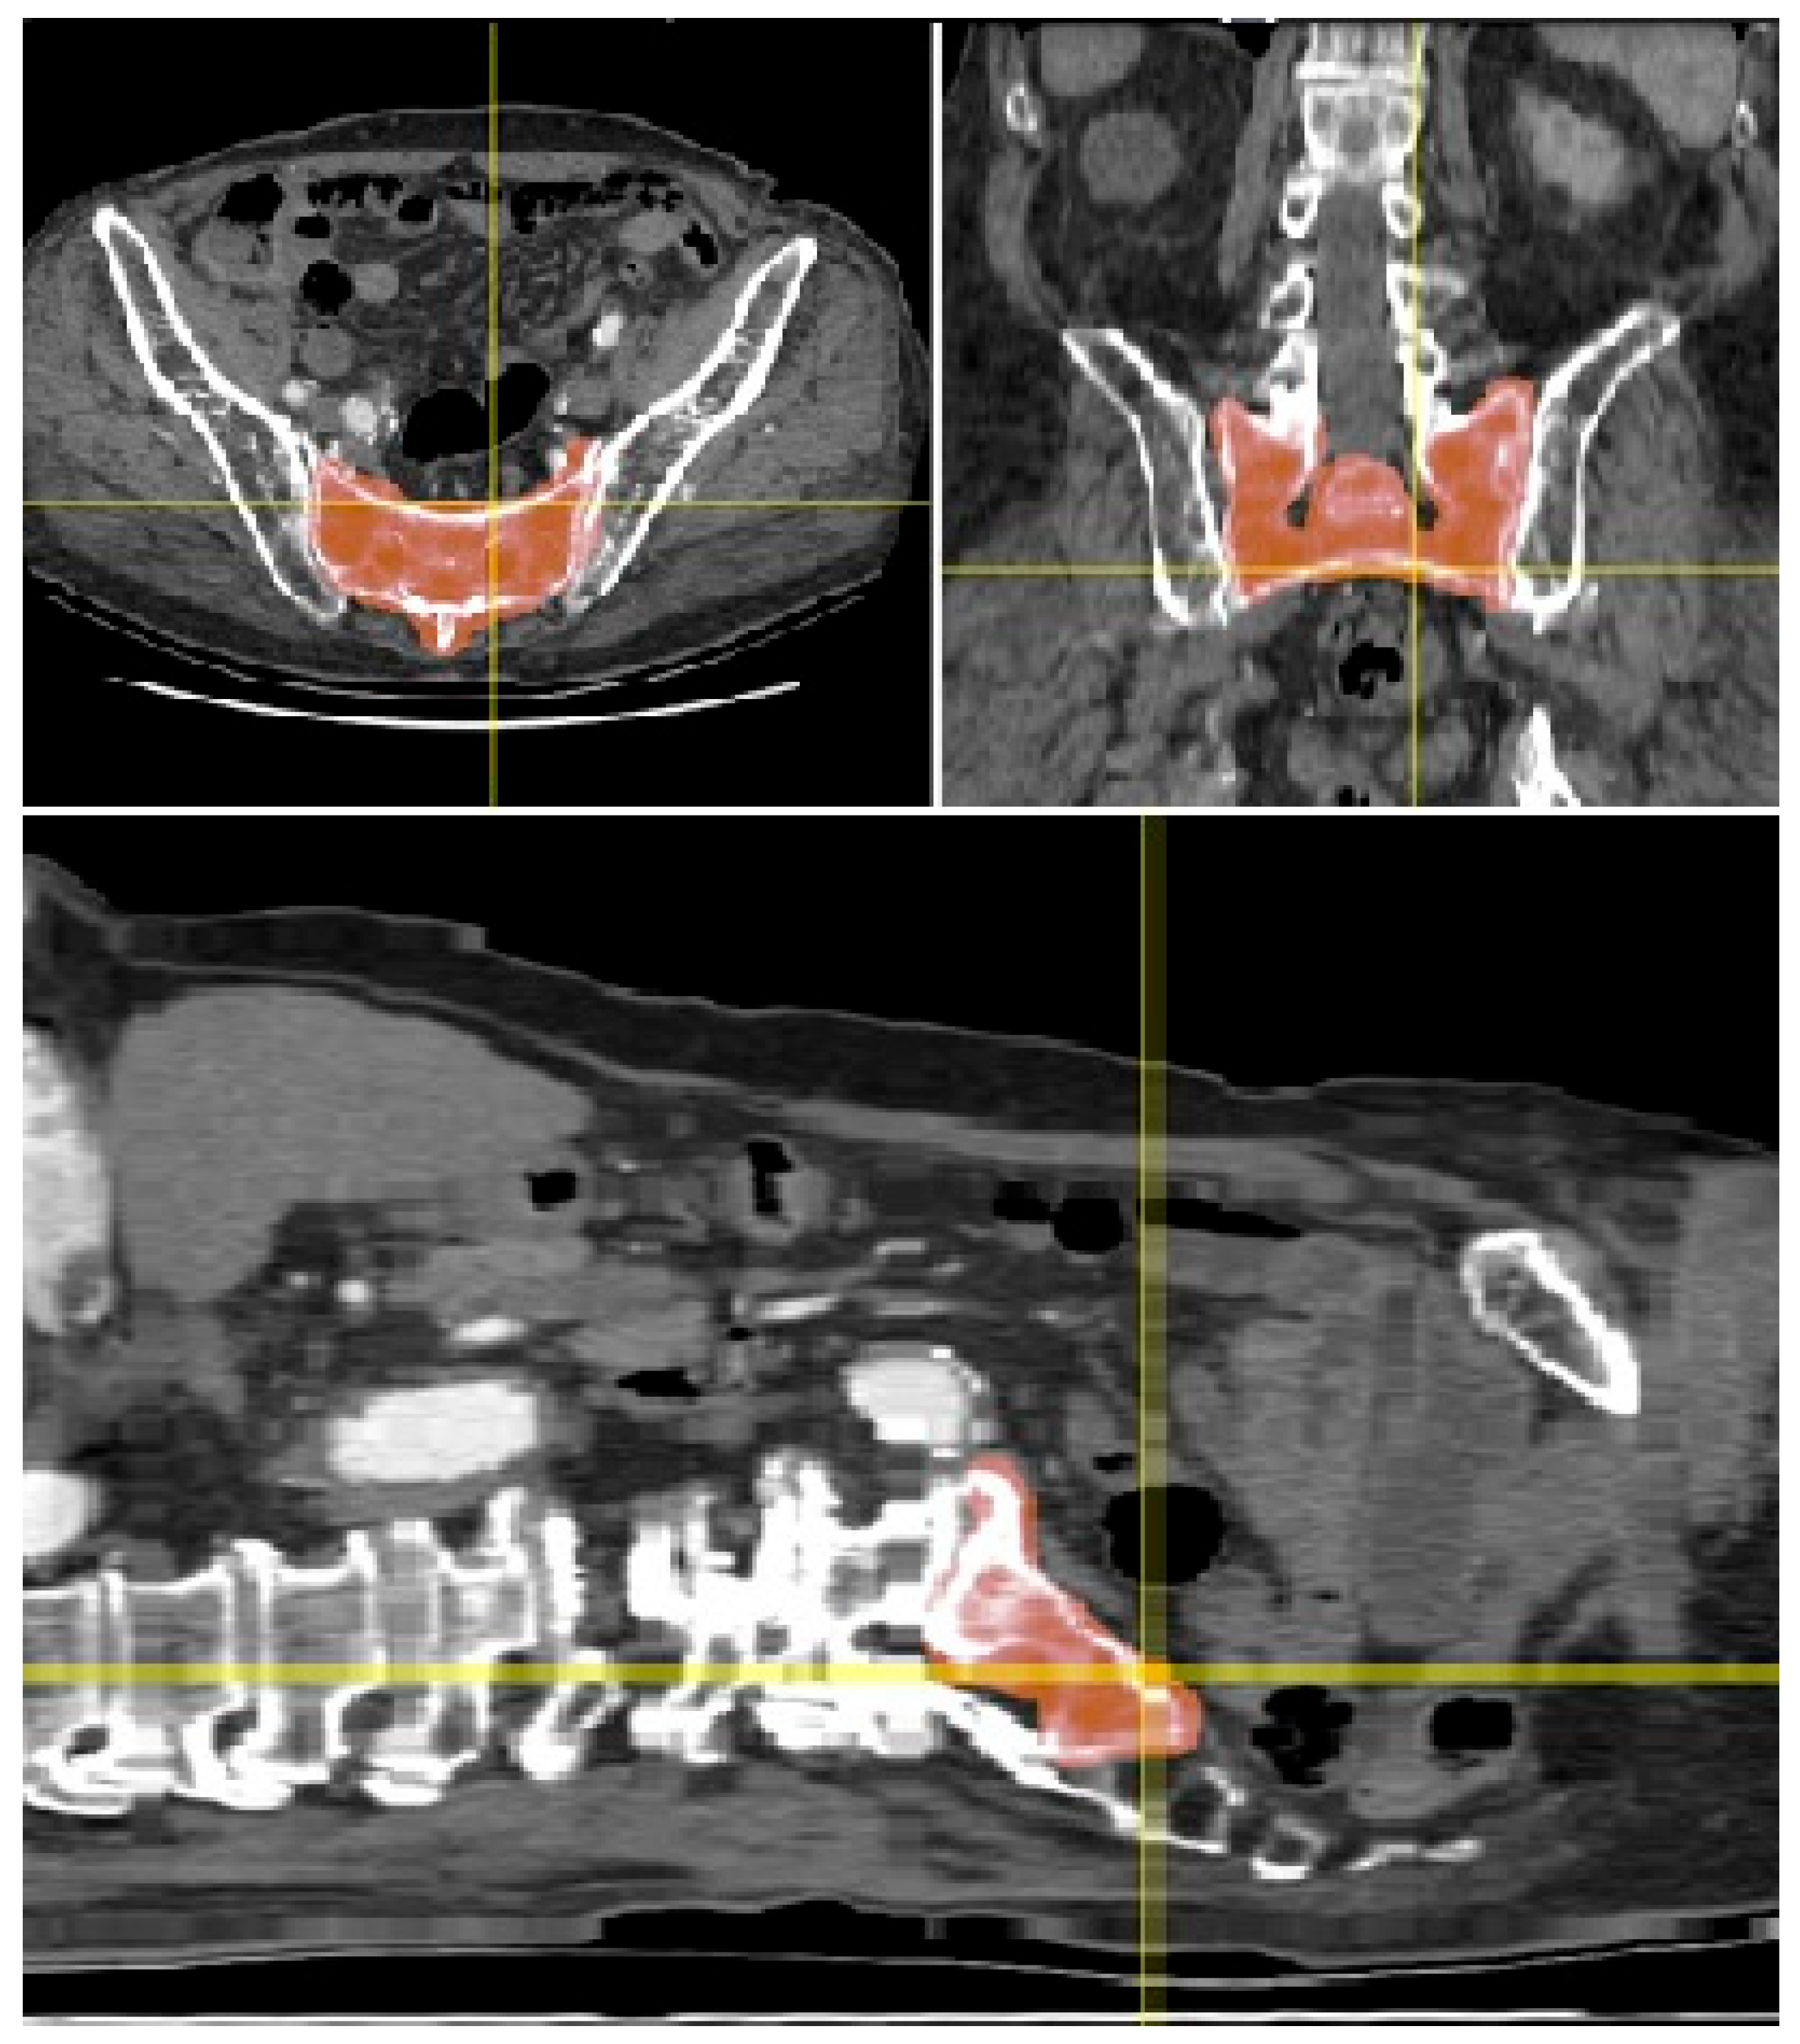

- CT Data Acquisition: The original CT scan dataset was provided for processing and analysis. The scan quality was sufficient, showing no relevant bony deformities or pathological changes in the sacrum and SI region, allowing for accurate 3D modeling.

- Manual Segmentation: Initial segmentation of the SI region was performed manually using Avizo software (version 2020.3, Thermo Fisher Scientific, Waltham, MA, USA). Standard thresholding techniques were attempted; however, due to the relatively low bone density in the SI region, these methods were ineffective in accurately delineating the joint.

- Freehand Segmentation: To overcome the limitations posed by the low-density bone structure, a freehand segmentation approach was employed. This method, which involved manually tracing the boundaries of the SI region, took approximately one hour to complete. The result was a high-precision binary mask of the SI region, which was then used to create an accurate 3D model of the joint.

3.1. Three-Dimensional Model Creation and Segmentation